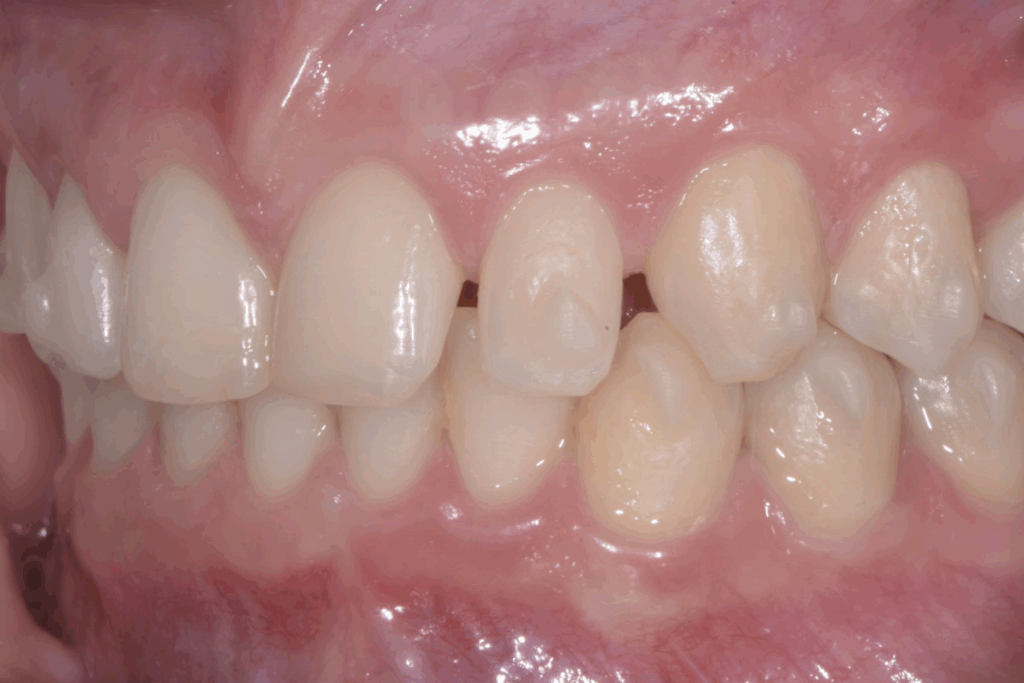

A 17 anni, una paziente si è rivolta al nostro studio con l’obiettivo di migliorare il proprio sorriso e la funzionalità masticatoria. Il caso clinico presentava una combinazione di problematiche comuni e complesse: agenesia dei settimi inferiori, incisivi superiori di piccole dimensioni e un morso profondo. Questa situazione non solo comprometteva l’estetica del sorriso, ma poteva causare problemi funzionali a lungo termine. La soluzione scelta per questa giovane paziente è stata un approccio combinato di ortodonzia moderna con allineatori trasparenti e odontoiatria estetica conservativa.

La prima fase del trattamento è stata un’analisi approfondita. Durante il check-up, abbiamo confermato la diagnosi di agenesia dei secondi molari permanenti inferiori, una condizione congenita che lascia spazi vuoti nell’arcata. Abbiamo inoltre rilevato che gli incisivi superiori erano di dimensioni ridotte rispetto al resto dei denti e che la paziente presentava un morso profondo, con gli incisivi superiori che coprivano eccessivamente quelli inferiori. Questa valutazione completa ci ha permesso di creare un piano di trattamento personalizzato e preciso, tenendo conto di tutte le problematiche presenti.

Per affrontare le sfide del caso, abbiamo optato per l’utilizzo di allineatori trasparenti. Questo tipo di trattamento è stato scelto per la sua efficacia nel muovere i denti in modo preciso e graduale, ma anche per la sua discrezione, fondamentale per una paziente in età scolare. Il piano di trattamento ha previsto una serie di allineatori personalizzati, che la paziente doveva sostituire con il passare delle settimane.

- Chiusura degli spazi: gli allineatori sono stati programmati per spostare i denti posteriori e chiudere gli spazi vuoti lasciati dall’agenesia dei settimi, evitando la necessità di impianti o ponti.

- Correzione della verticalità: il trattamento ha lavorato per estrusione e intrusione selettiva di alcuni denti, al fine di correggere il morso profondo e ristabilire una corretta occlusione.

- Preparazione estetica: una volta raggiunta la corretta posizione dei denti, il trattamento ha preparato lo spazio e l’allineamento ideali per la fase successiva.